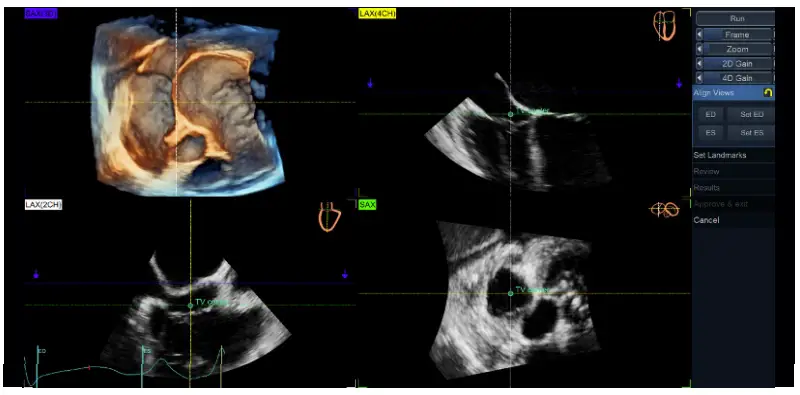

Align Views: - Place the TV center landmark at the center of TV annulus in both 4-chamber [LAX(4CH) – yellow] and the orthogonal view [LAX(2CH)) – white], as well as in the short-axis (SAX– green) view.

- Position the longitudinal axis of the RV to intersect the RV apex and the center of TV annulus in both 4CH and 2CH, as indicated in the miniature drawings shown in the right upper corner of each image

- The transversal green plane should be positioned at the TV annulus level, crossing approximately the leaflet hinges in each view (due to the saddle shape of the annulus, the plane position cannot be perfectly aligned with the 4 annulus points in both views simultaneously).

- The blue plane corresponds with the rendered SAX3D (upper left image) and it is generally recommended to be positioned on the ventricular side of the TV for TTE and on atrial side for TEE (Figure 3), close to the valve, to allow a proper visualization of the TV leaflet morphology and its spatial relationship with surrounding anatomic structures to facilitate the orientation of the user (Figure 4)

Figure 5. TV quad view showing the alignment of the views and planes with 4D Auto TVQ on a transesophageal TV data set